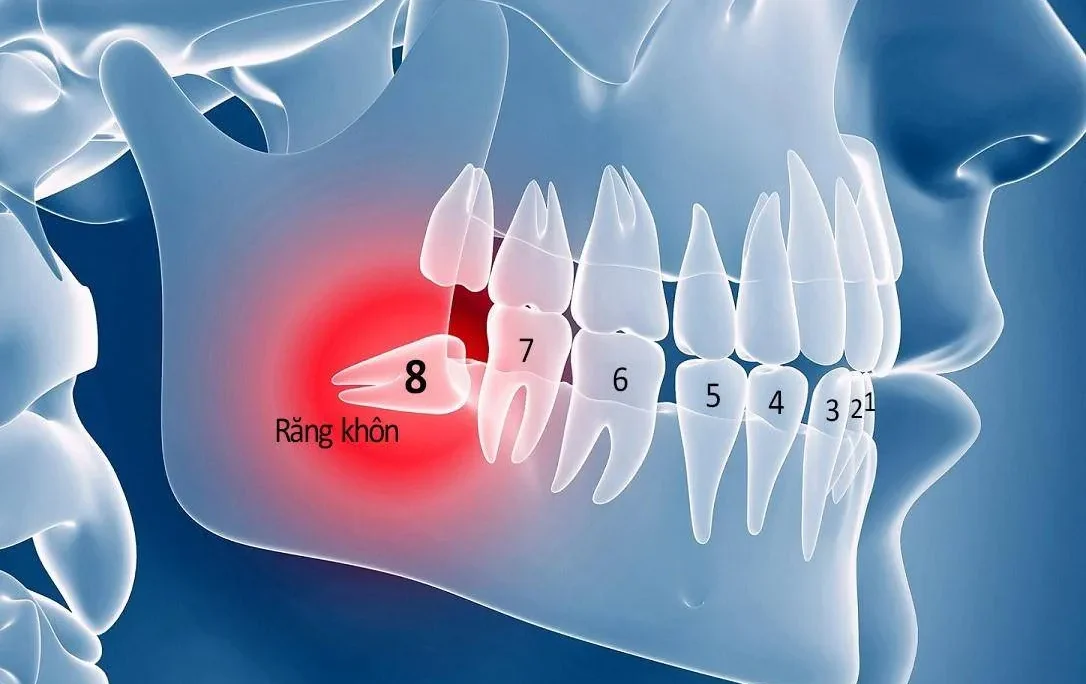

Răng khôn mọc lệch

Răng khôn (hay còn gọi là răng số 8) là chiếc răng cuối cùng mọc lên trong hàm răng. Chiếc răng thường xuất hiện khi xương hàm đã phát triển hoàn thiện. Lúc này khi răng khôn mọc thì phần lợi không còn nhiều không gian. Nếu hàm răng không đủ chỗ để răng khôn mọc lên đúng vị trí, răng sẽ có nguy cơ mọc lệch. Thậm chí răng có thể mọc ngầm hoặc đâm vào răng bên cạnh. Tình trạng này không chỉ gây đau nhức mà còn có thể dẫn đến viêm lợi trùm. Lúc này phần nướu che phủ răng bị viêm do cọ xát hoặc nhiễm trùng.